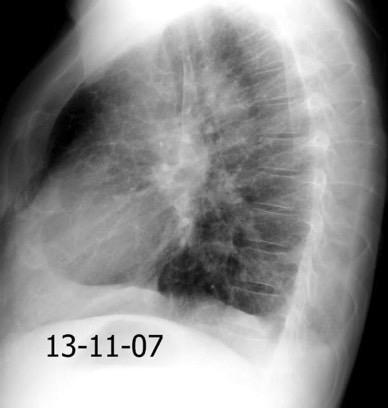

Neumonía a neumococos base izda. con derrame que aumenta.

Broncograma en lateral y en US.

(36-66% en ingresados)